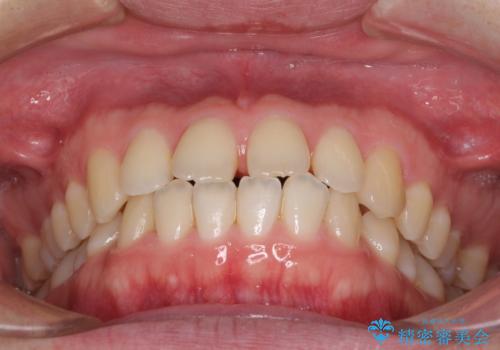

- 上の前歯の隙間を気にして来院された患者様です。

インビザラインにより、上下の歯列を側方に拡大しつつ、前歯の隙間を閉じていくこととしました。

1日22時間の装着時間をしっかりと守ってくださったので、隙間がきれいに閉じ、口元の突出感も改善することができました。